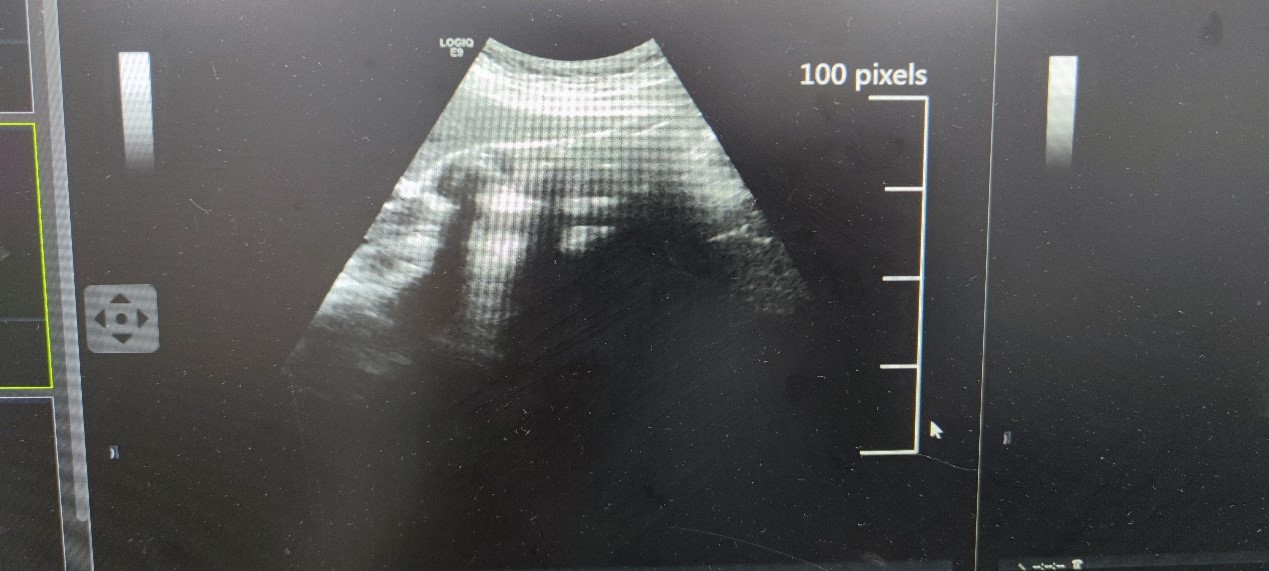

胆石症是肝胆外科常见疾病。数十年前,因缺乏合适的辅助检查手段,胆石症的诊断主要依靠患者的症状和体征。因此,当患者出现典型的“Murphy氏”体征时,临床医生才更有把握进行诊断。而该诊断过程中患者承担着巨大痛苦,相当部分患者手术时已出现胆囊化脓或者坏疽,手术过程中很可能导致患者腹腔感染或者胆道损伤。随着物理学超声波科技的发展,尤其是B型超声应用于临床检查,医生能够在患者出现轻微腹部症状时进行胆石症的诊断并及时进行外科手术,使患者免受巨大痛苦,也降低了手术风险。当下,超声技术、X线断层影像、磁共振断层影像和三维合成影像等创新性科学技术的发展,使临床医生有了更多武器对胆囊结石、肝内外胆管结石进行准确诊断,并在患者出现症状前进行外科干预。尤其是近年来,国内三维合成影像学成像技术的迅速发展,促进了外科疾病诊疗的便利化。在临床实践实习中,教学团队通过为学生讲解胆石症的诊断历程,鼓励学生在学科领域的临床工作和疾病科学研究中勇于探索,积极改善临床诊疗技术,助力医疗卫生事业发展,培养学生求真务实、开拓创新的科学精神。